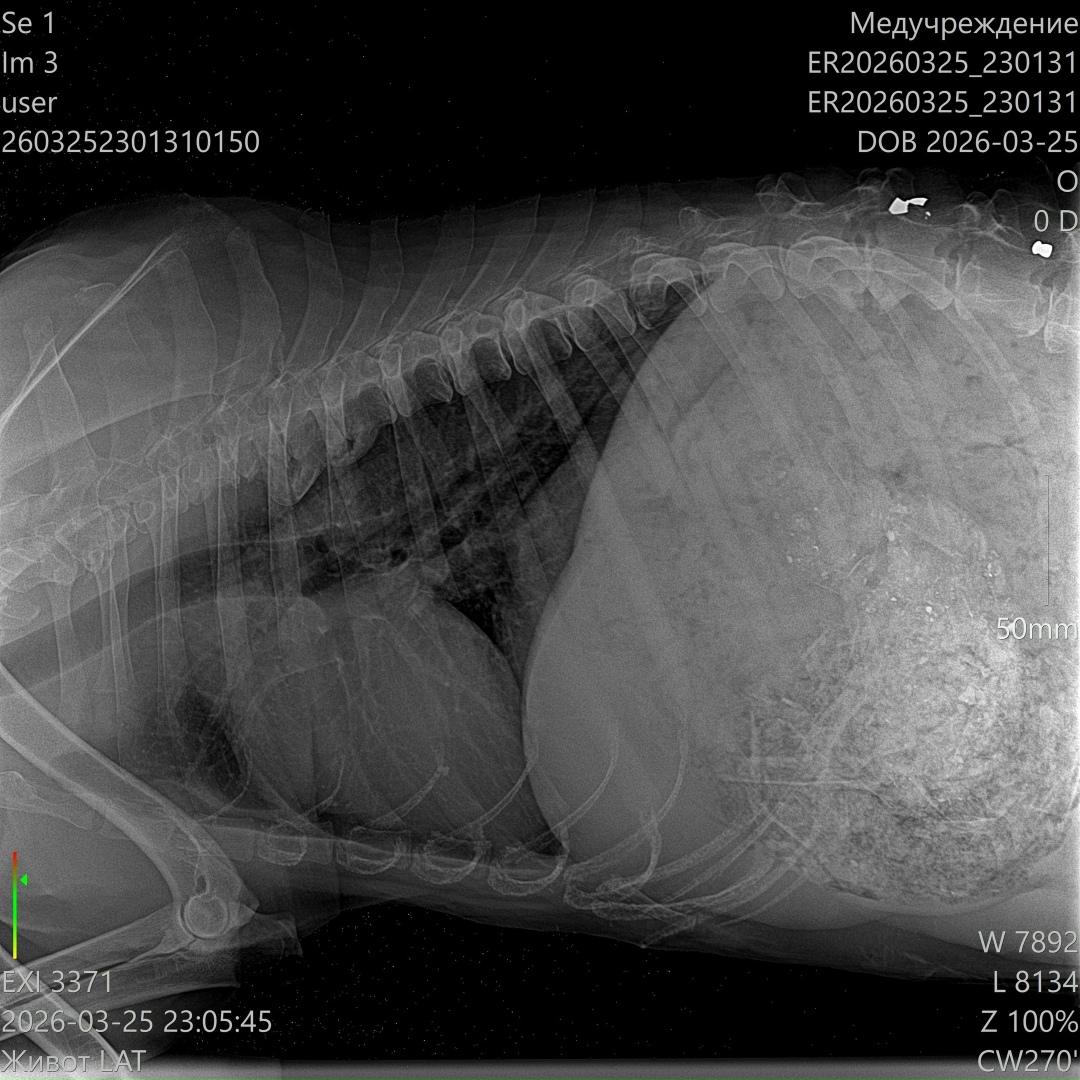

Сейчас он в клинике в тяжёлом состоянии: высокая температура, сильно повышены лейкоциты. По УЗИ свободной жидкости нет, но в желудке — куча костей… и самое страшное — пуля в позвоночнике 😭